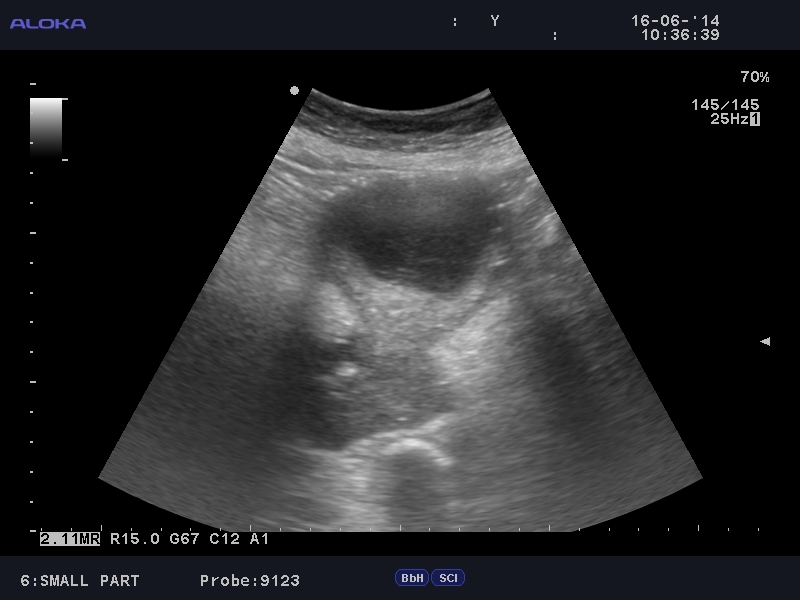

Пожилая женщина, выявлен уретерогидронефроз справа.

Рак шейки матки, правосторонний гидроуретеронефроз.

Доказано морфологически.